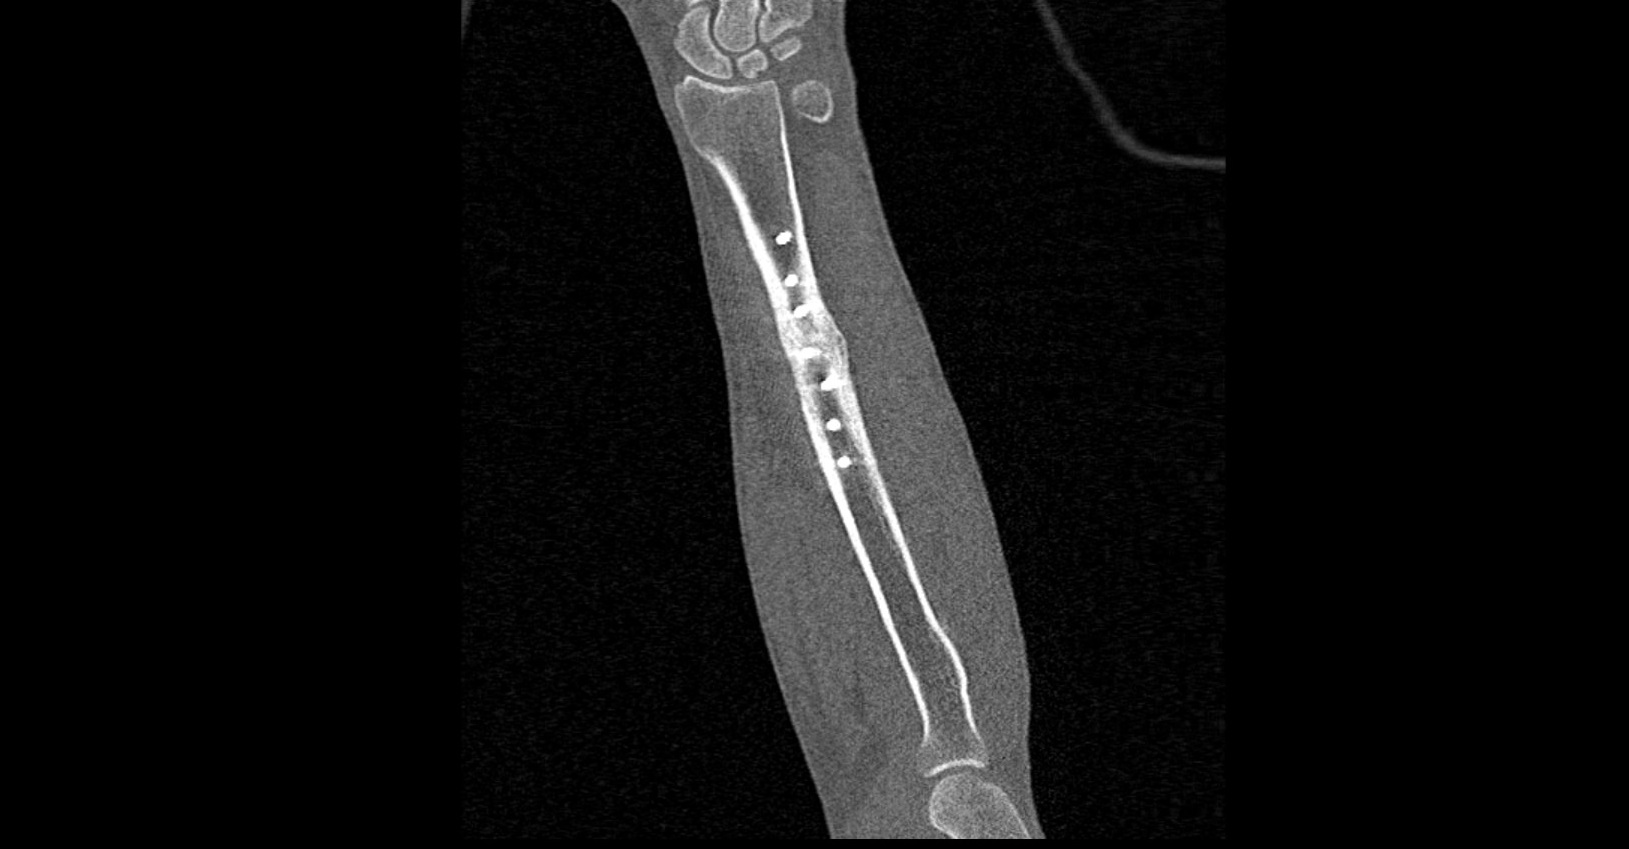

Мультиспиральная компьютерная томография является наиболее точным и информативным методом диагностики патологии предплечья. Метод КТ основан на применении рентгеновского излучения и лучше всего подходит для оценки состояния костных структур, так как кости в большей степени поглощают рентгеновские лучи и ярко визуализируются на снимках.

В диагностических центрах «Доступная медицина» сканирование области предплечья проводится на современных мультиспиральных компьютерных томографах экспертного класса TOSHIBA AQUILION. Аппараты при помощи рентгеновских лучей послойно сканируют исследуемую область, делая одномоментно множество тончайших срезов толщиной от 0,5 мм. В результате получаются детализированные изображения высокого уровня четкости и контрастности, при этом томографы обеспечивают минимум лучевой нагрузки на организм пациента.

Полученные при сканировании данные в дальнейшем проходят цифровую обработку, и на их основе создаются трехмерные изображения области предплечья.

Мультиспиральная КТ позволяет диагностировать деформации костей на фоне аномалий развития, различные вывихи, переломы костей предплечья, ушибы мягких тканей и надкостницы. КТ помогает обнаружить участки деструкции костной ткани, воспалительные изменения, опухолевые процессы. Результаты КТ дают информацию для хирурга и травматолога перед операцией о расположении осколков кости, а после операции позволяют оценить правильность репозиции костных отломков, проследить процессы регенерации кости, вовремя выявить различные осложнения (воспаление, смещение отломков, очаги деструкции костной ткани).